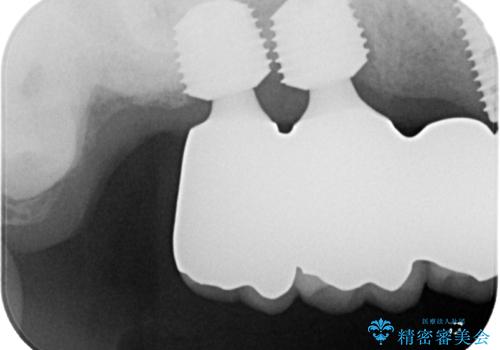

ブリッジの土台となっている歯は全て抜歯が必要な状態であったため、事前に仮歯を用意して、極力抜歯と同時にインプラントを埋入し、速やかに仮歯を装着して噛めるように処置を進めて行くこととしました。

手前の歯は骨の欠損が著しいため、抜歯後暫く待ってから埋入を行うこととしました。

インプラントが無事に生着した後に、オールセラミッククラウンにて補綴治療を行うこととしました。

後方2本を先に埋入し、即日で仮歯を装着しましたが、徐々にインプラントが骨内で緩んでしまい、手前のインプラント埋入時に再埋入することとなりました。

再埋入後は緩くなることもなく、無事に補綴治療を行うことができました。